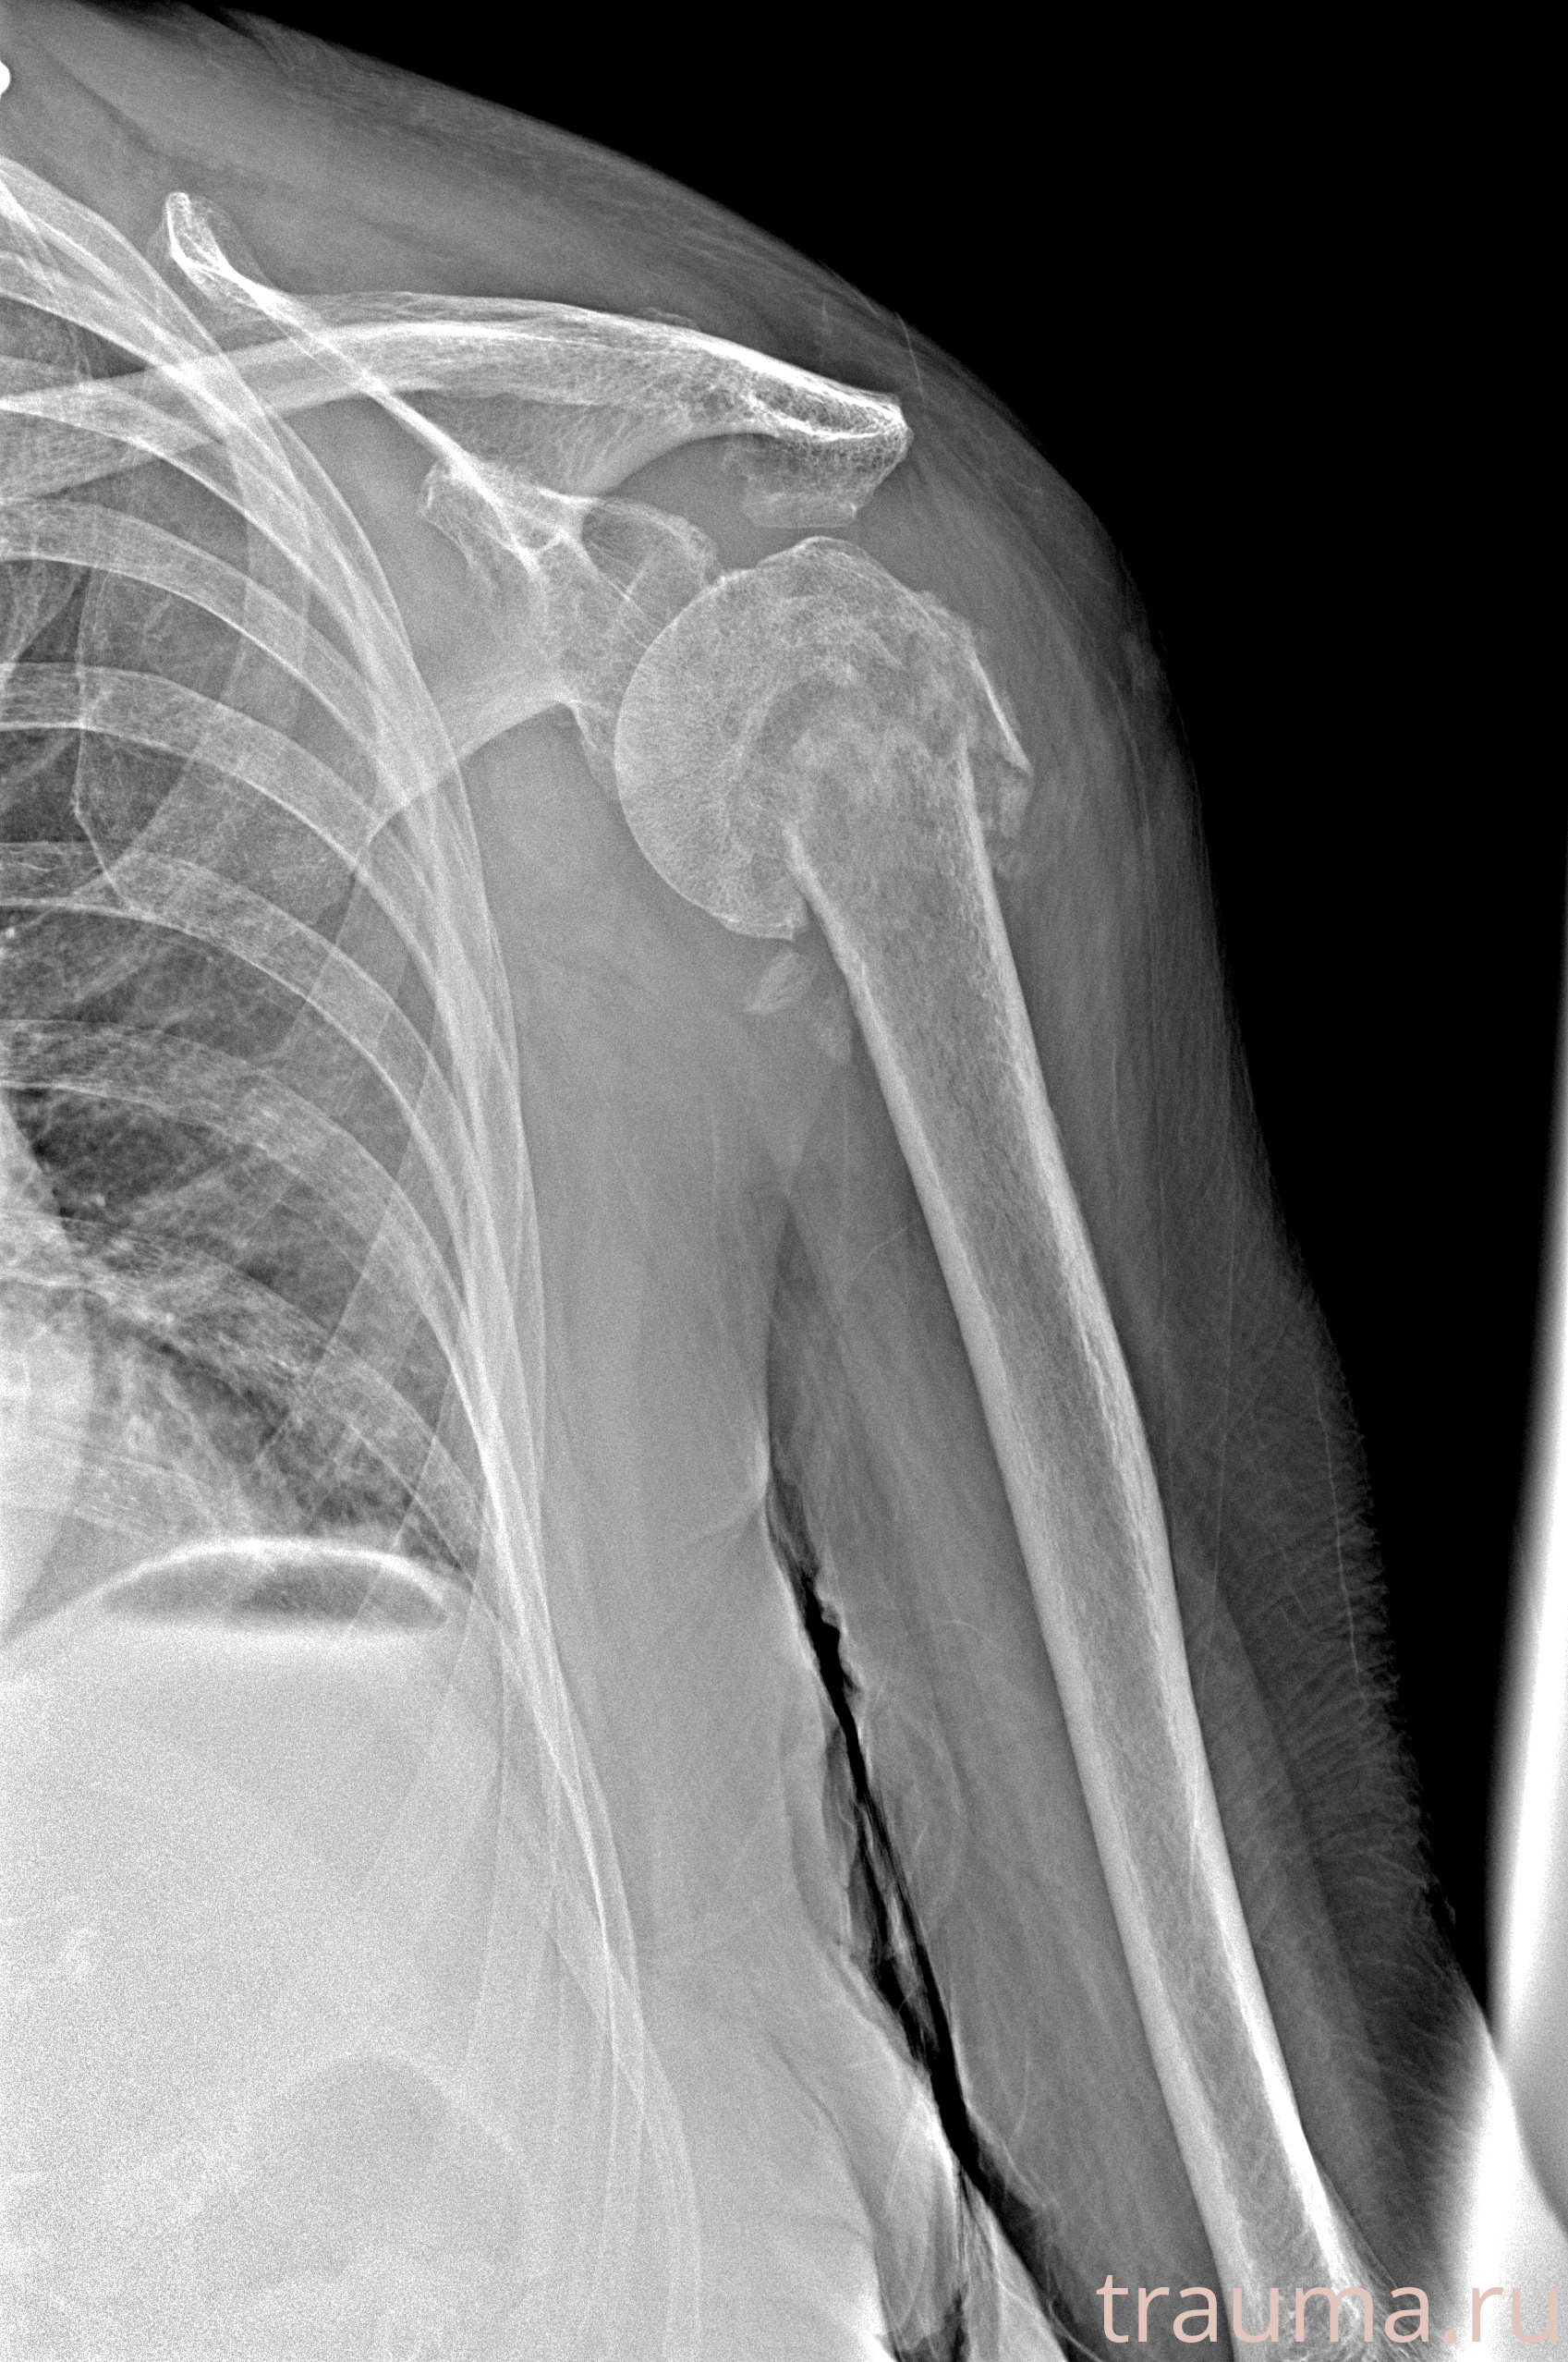

Рентгенограммы

Рентген на дому: по вашему адресу приезжает врач-рентгенолог, травматолог-ортопед с мобильным рентгеновским аппаратом, проводит диагностику травмы или заболевания, делает необходимые рентгенограммы, дает рекомендации по дальнейшему лечению. Получить качественные снимки в домашних условиях возможно благодаря уникальной методике, разработанной МосРентген Центром для института  Склифосовского